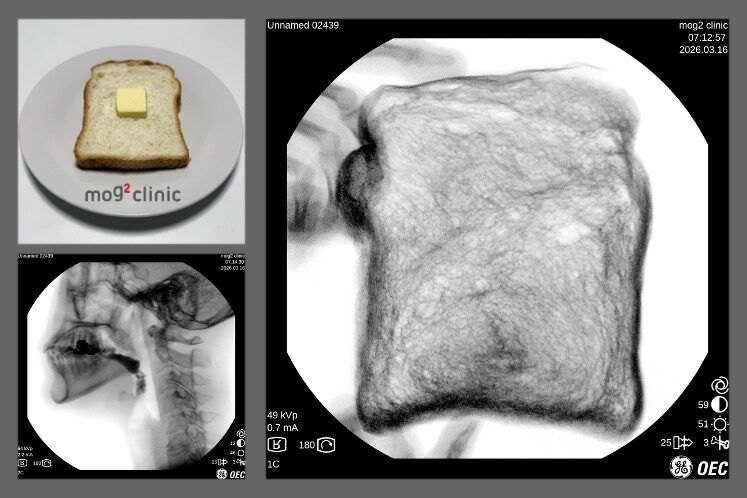

当クリニックでは2024年より食感が実際の食パンに近い、「バリウム食パン」を独自開発することで、摂食嚥下の一連の流れにおける全てのステージにおいて精度の高いVF検査を行ってまいりました。

今回の最新バージョンでは、造影剤として使用する硫酸バリウムの粒子特性をさらに改良しました。その結果、外観・香り・味・食感が実際の食パンと区別がつかないレベルの「改良バリウム食パン」の開発に成功し、検査食として使用を開始しています。

Since 2024, our clinic has independently developed a “Barium White Bread” with textural properties closely resembling those of standard white bread. This innovation has enabled highly accurate VF assessments across all stages of the swallowing process.

In this latest iteration, we have further refined the particle characteristics of barium sulfate used as the contrast agent. As a result, we have successfully developed an “Enhanced Barium White Bread” that is virtually indistinguishable from real bread in terms of appearance, aroma, taste, and texture. This improved test meal has now been introduced into clinical use.